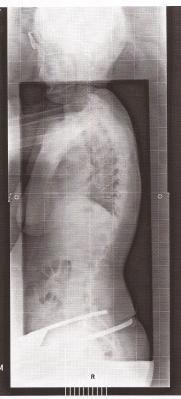

Du hast diesbezüglich bislang nur von Deiner Skoliose gesprochen, die offensichtlich bei Dr. Hoffmann mit einer frontalen Ganz-Aufnahme abgeklärt wurde. Hat es keine seitliche Ganz-Aufnahme gegeben?Außer der moralischen Seite habe ich noch ein Problem: meine Orhtopädin diagnostizierte einen ausgeprägten Hohl-Rundrücken, der dringend Muskelaufbau braucht; Dr. C. aus Bochum diagnostizierte einen ausgeprägten Flachrücken, den ich bei novotergum behandeln lassen soll; Dr. H. aus Leonberg hat mir einen völlig gesunden Rücken diagnostiziert und ich soll auf keinen Fall Muskelaufbau machen. Was denn nun???

Ja eine seitliche Ganzaufnahme wurde auch gemacht, eine frontale Ganzaufnahme außerdem und mein Becken im Liegen.

Und was hat er denn nun zu dieser Aufnahme gesagt ?lenaluna hat geschrieben:Ja eine seitliche Ganzaufnahme wurde auch gemacht, ....

Also einen Flachrücken sehe ich da nun wirklich nicht, eher einen ganz leichten Rundrücken und vor allen dingen das deutliche Hohlkreuz, was optisch wohl nicht so in den Vordergrund triit, im Gegensatz zu den Wirbelkörpern. Die HWS sieht man leider nicht, da könnte evtl. auch ein Anteil des Ausgleichs des Hohlkreuzes liegenlenaluna hat geschrieben:meine Orhtopädin diagnostizierte einen ausgeprägten Hohl-Rundrücken, der dringend Muskelaufbau braucht; Dr. C. aus Bochum diagnostizierte einen ausgeprägten Flachrücken, den ich bei novotergum behandeln lassen soll; Dr. H. aus Leonberg hat mir einen völlig gesunden Rücken diagnostiziert

Und die Aussage von Dr. Hoffmann über "völlig gesund" ist bezüglich der frontalen Aufnahme gemeint oder ?

Also da muss ich passen, ich sehe eine Hyperlordose (Hohlkreuz).Keine Hyoerkyphose oder -Lordose

Ist ja durchaus möglich und wenn man durch intensive Dehnung die "Hohlkreuz" Situation verbessern kann, ist das möglicherweise kein Hohlkreuz per Definition.

Hat Dr. Hoffmann versucht, durch entsprechenden Druck Dich in diesem Bereich aufzurichten?

Anhand des Röntgenbildes hätte ich eher gedacht, dass Deine optische Figur weniger ein "Hohlkreuz" aufweist, als die tatsächliche Stellung der Wirbelkörper.Aber meine Figur ist eher Hohlkreuz: Po sticht nach hinten raus und der Bauch nach vorne.

Aber bitte, das ist alles meine persönliche Spekulation.